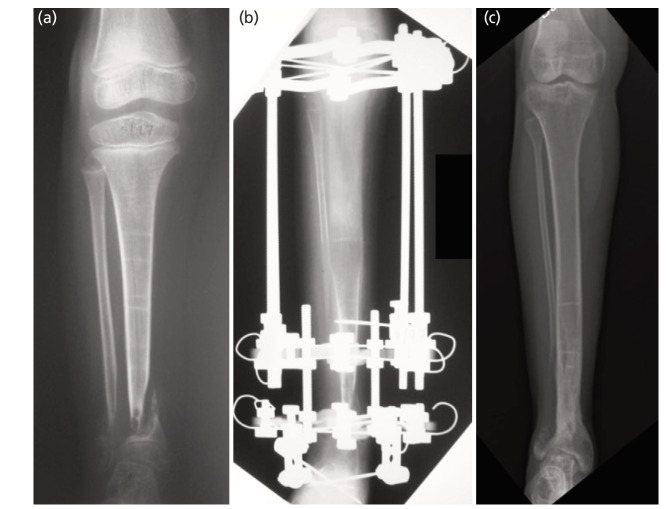

Results: Twelve patients (13 tibiae) were reviewed with an average follow-up of 14.5 years (range 3.1-24.0 years). Nine (69.2%) tibiae underwent intramedullary (IM) rodding; two (15.4%) were stabilised with the Ilizarov external fixator (IEF) + IM rod; and two other (15.4%) tibiae with the IEF only. Primary union was achieved in 5 (38.5%) tibiae, but refractures occurred in two tibiae (40%), lowering the overall success rate to 23.1%. Fixation with IM rodding alone led to a low primary union rate (22.2%) but combining it with IEF avoided refracture. Seven (53.8%) tibiae reached skeletal maturity and had a union at 12.6 years (7.5-17.4 years), after an average of 3 surgical procedures. Four (57.1%) were Johnston Grade I, and 3 (42.9%) were Grade II. Four (57.1%) tibiae had residual tibial valgus, two (28.6%) tibial varus, four (57.1%) procurvatum and one (14.3%) recurvatum. The average LLD was 3.9cm (2-10cm).

Conclusion: Intramedullary rodding alone is ineffective for producing a bony union but combining it with IEF minimise the refracture rate. The chances of union increased with age, but residual deformity and shortening are an ongoing challenge.